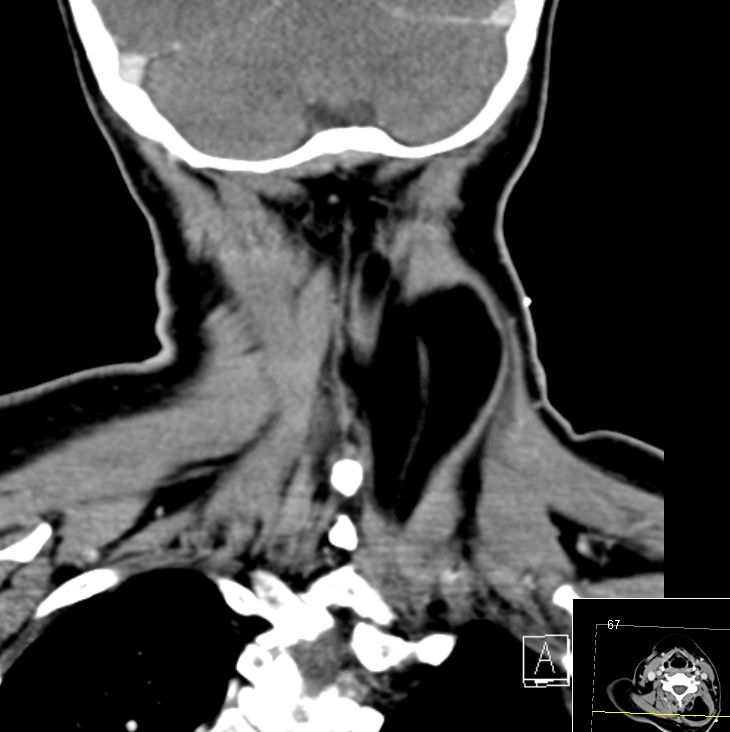

67-jährige Patientin mit einer Raumforderung im Nacken. Das CT zeigt eine fettdichte Struktur innerhalb der dorsalen Halsmuskulatur.